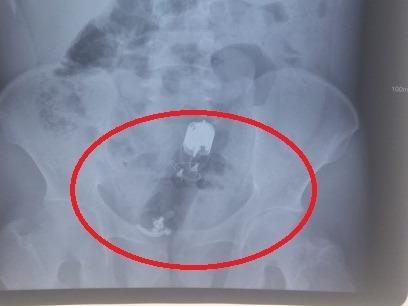

Đau tức hậu môn, không thể đi đại tiện 3 ngày, anh Quang đến bệnh viện kiểm tra. Các bác sĩ phát hiện dị vật dài 18 cm nằm sâu trong trực tràng.